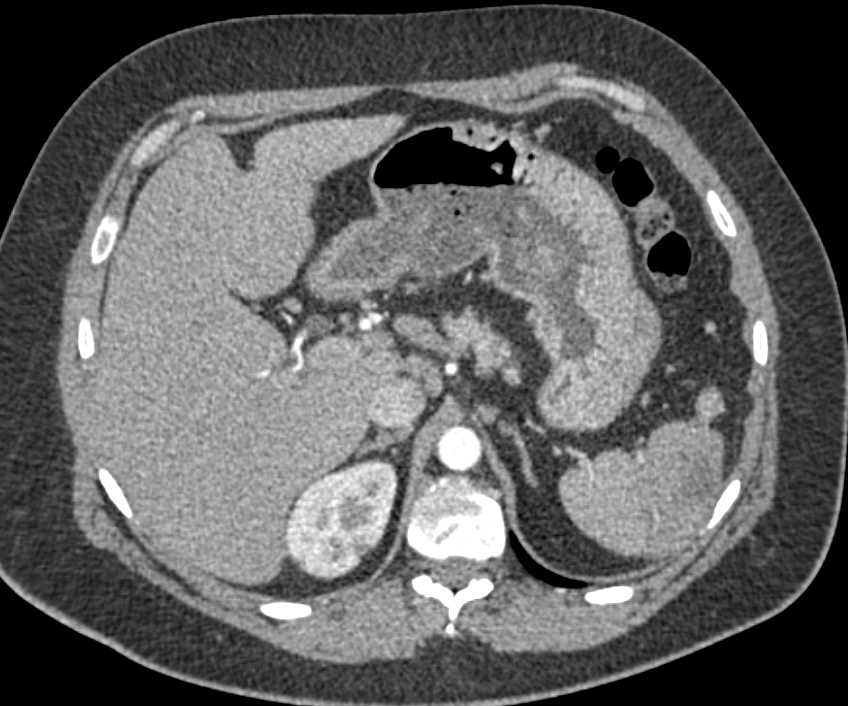

Vascular Metastases to the Liver, Bone and Muscle from Renal Cell Carcinoma